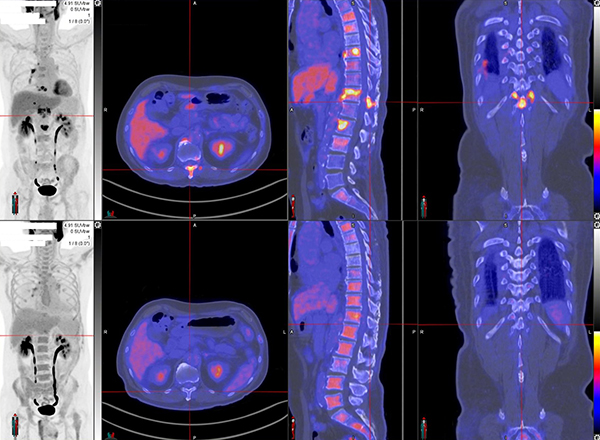

崭新的疗诊合一运用相同放射性药物作诊断及治疗:针对治疗扫描影像上的肿瘤。它利用特定的示踪剂,首先在诊断扫描时得知其分布,模拟治疗的情况,并且带来预计成效的参数以作进一步规划。然後在治疗时,使用相同特性的示踪剂把达到治疗效果的辐射量准确地带到肿瘤,完成後的扫描亦能直接量化肿瘤吸收的活跃度,评估整体成效及分析进行下一次治疗的可行性。

应用例子有 镓-68/鑥-177胜肽金属错合物(DOTA Conjugated Peptides)神经及内分泌肿瘤治疗丶镓-68/氟-18与鑥-177前列腺特异性膜抗原(PSMA)癌治疗 及 鍀-99m/钇-90微粒肝肿瘤治疗。请点击此处了解放射核素治疗。

多种追踪剂用於分辨肝肿瘤的病理特性 - 癌症相关的成纤维细胞 (Ga-68 FAPI 吸收)

[C-11] Acetate及[F-18] FDG 分辨高分化及低分化肝癌